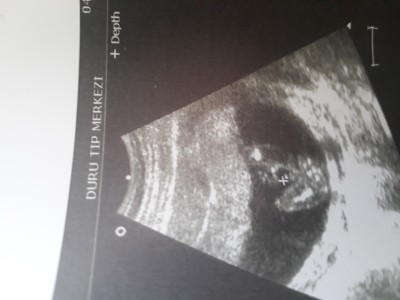

Sürekli yazıları okuyordum cinsiyet konusunda cok heyecanlıydım 2 kizim vardi cok şükür simdi de hamile olunca birde oğlum olsun istiyordum Allah herkezin gönlüne göre versin dün kan sonuçlarımı aldim hem iyi cikti hemde cinsiyetini öğrendim erkek dedi net bi sekilde hatta resmini bile çekti doktor pipinin bende sizle paylasmak istedim Allah sağlıklı sıhhatli Hayirli evlatlar nasip etsin Hayirli kolay doğumlarımız olsun insAllah

Gebelik haftası 16.1